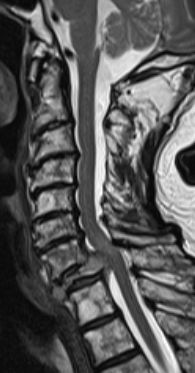

bildgebende Diagnostik